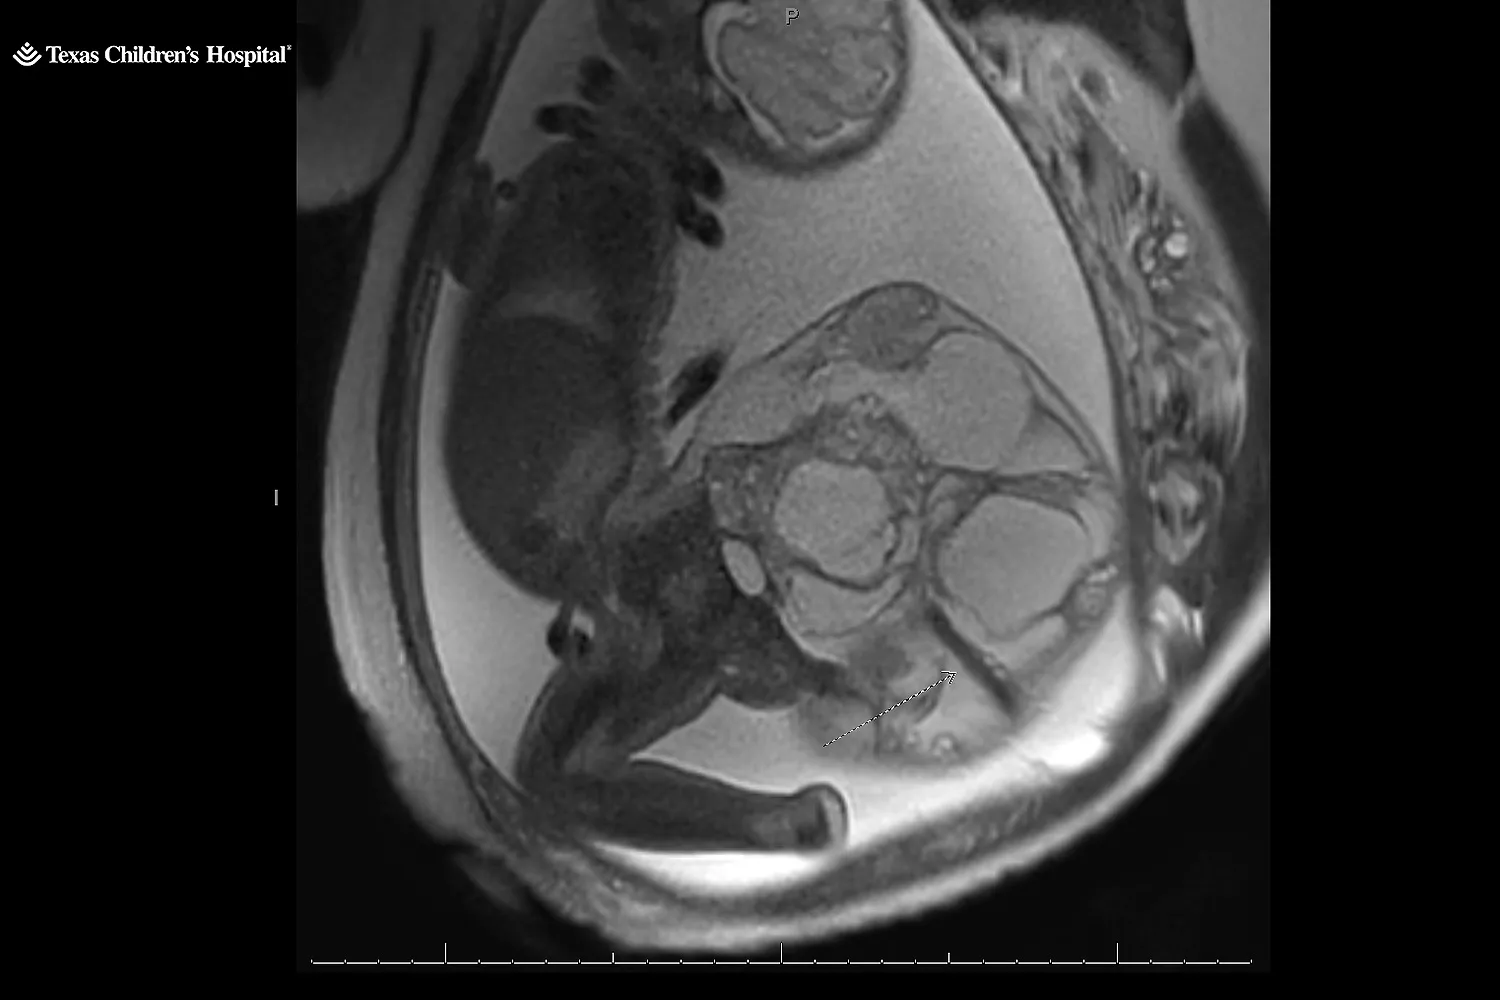

Την επόμενη μέρα, ένας ειδικός διέγνωσε ότι το κοριτσάκι τους δεν είχε δισχιδή ράχη, αλλά ένα σπάνιο εμβρυϊκό όγκο, το ιεροκοκκυγικό τεράτωμα, που σχηματίζεται από τον κόκκυγα του μωρού. Το ιεροκοκκυγικό τεράτωμα εμφανίζεται σε μία στις 20.000 γεννήσεις. Το ζευγάρι παραπέμφθηκε στο Texas Children’s Pavilion for Women στο Χιούστον για να παρακολουθείται από εξειδικευμένη ιατρική ομάδα.

Ταξίδεψαν 245 μίλια από το σπίτι τους για να συναντήσουν τον Dr. Ahmed Nassr, ειδικό σε εμβρυομητρική ιατρική και χειρουργό στο Texas Children’s Pavilion for Women. Ο Nassr τους εξήγησε ότι ο όγκος ήταν «πολύ σπάνιος». Μάθανε ότι εμφανίζεται συχνότερα σε κορίτσια παρά σε αγόρια και ότι συνήθως είναι καλοήθης. Ωστόσο, οι γιατροί δεν γνωρίζουν πάντα γιατί συμβαίνει.

«Είναι απλώς κακή τύχη», λέει ο Nassr. Οι όγκοι αυτοί μπορούν να γίνουν πολύ μεγάλοι και, καθώς αναπτύσσονται, μπορεί να δημιουργήσουν μεγάλα αιμοφόρα αγγεία. «Στην ουσία κλέβουν από το μωρό το αίμα που χρειάζεται», εξηγεί ο Nassr. «Η καρδιά του μωρού πρέπει να δουλέψει πολύ σκληρά» για να ανταποκριθεί, κάτι που μπορεί να οδηγήσει σε καρδιακή ανεπάρκεια.

Στις 21 Μαΐου, στις 34 εβδομάδες, η Kristin γέννησε με καισαρική. Η μικρή Adalida γεννήθηκε με έναν όγκο 16 εκατοστών, που ζύγιζε περίπου 1,8 κιλά – σχεδόν τα δύο τρίτα του σωματικού της βάρους.

Συνολικά, το μωρό και ο όγκος ζύγιζαν πάνω από 4,5 κιλά. Ο Nassr περιγράφει το μέγεθος του όγκου ως «λίγο μικρότερο από ένα καρπούζι, αλλά μεγαλύτερο από ένα πεπόνι». «Ήταν ένας μεγάλος όγκος, γι’ αυτό ανησυχούσαμε τόσο πολύ», λέει.